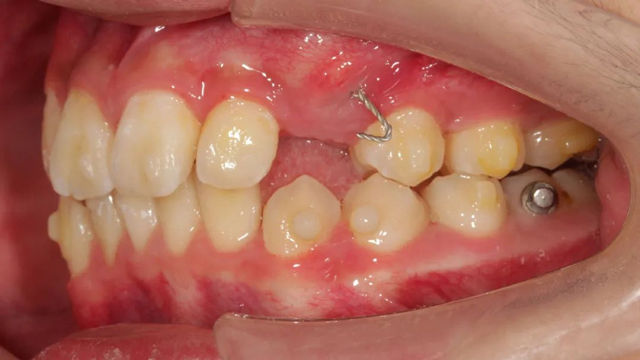

談到具體的治療方案,王亞楠醫(yī)生表示,整體的治療步驟是先拔除多生牙,一周后拆線,拆線當(dāng)天拔除滯留乳牙,并對(duì)埋伏阻生尖牙行開(kāi)窗術(shù),通過(guò)粘貼牽引扣進(jìn)行牽引,一周后開(kāi)始佩戴隱形牙套。

據(jù)介紹,這個(gè)病例最復(fù)雜之處就是阻生牙的牽引。從矯正開(kāi)始,醫(yī)生以目標(biāo)為向?qū)е贫ǔC正步驟,利用隱形牙套的優(yōu)勢(shì),以及牙根可視化引導(dǎo)牙齒走向目標(biāo)位,過(guò)程中密切關(guān)注阻生尖牙的方向及萌出情況,治療過(guò)程中不斷根據(jù)具體情況進(jìn)行調(diào)整牽引方向和力的大小,牽引治療幾乎貫穿了矯正的全過(guò)程。

“由于這是一顆尖牙,外形比較圓潤(rùn),并且是口內(nèi)牙根最長(zhǎng)的牙齒,矯治器力不太容易表達(dá),所以移動(dòng)時(shí)會(huì)更難一些,從牙齒出齦到建頜,每一步都離不開(kāi)我們精心的設(shè)計(jì)。”